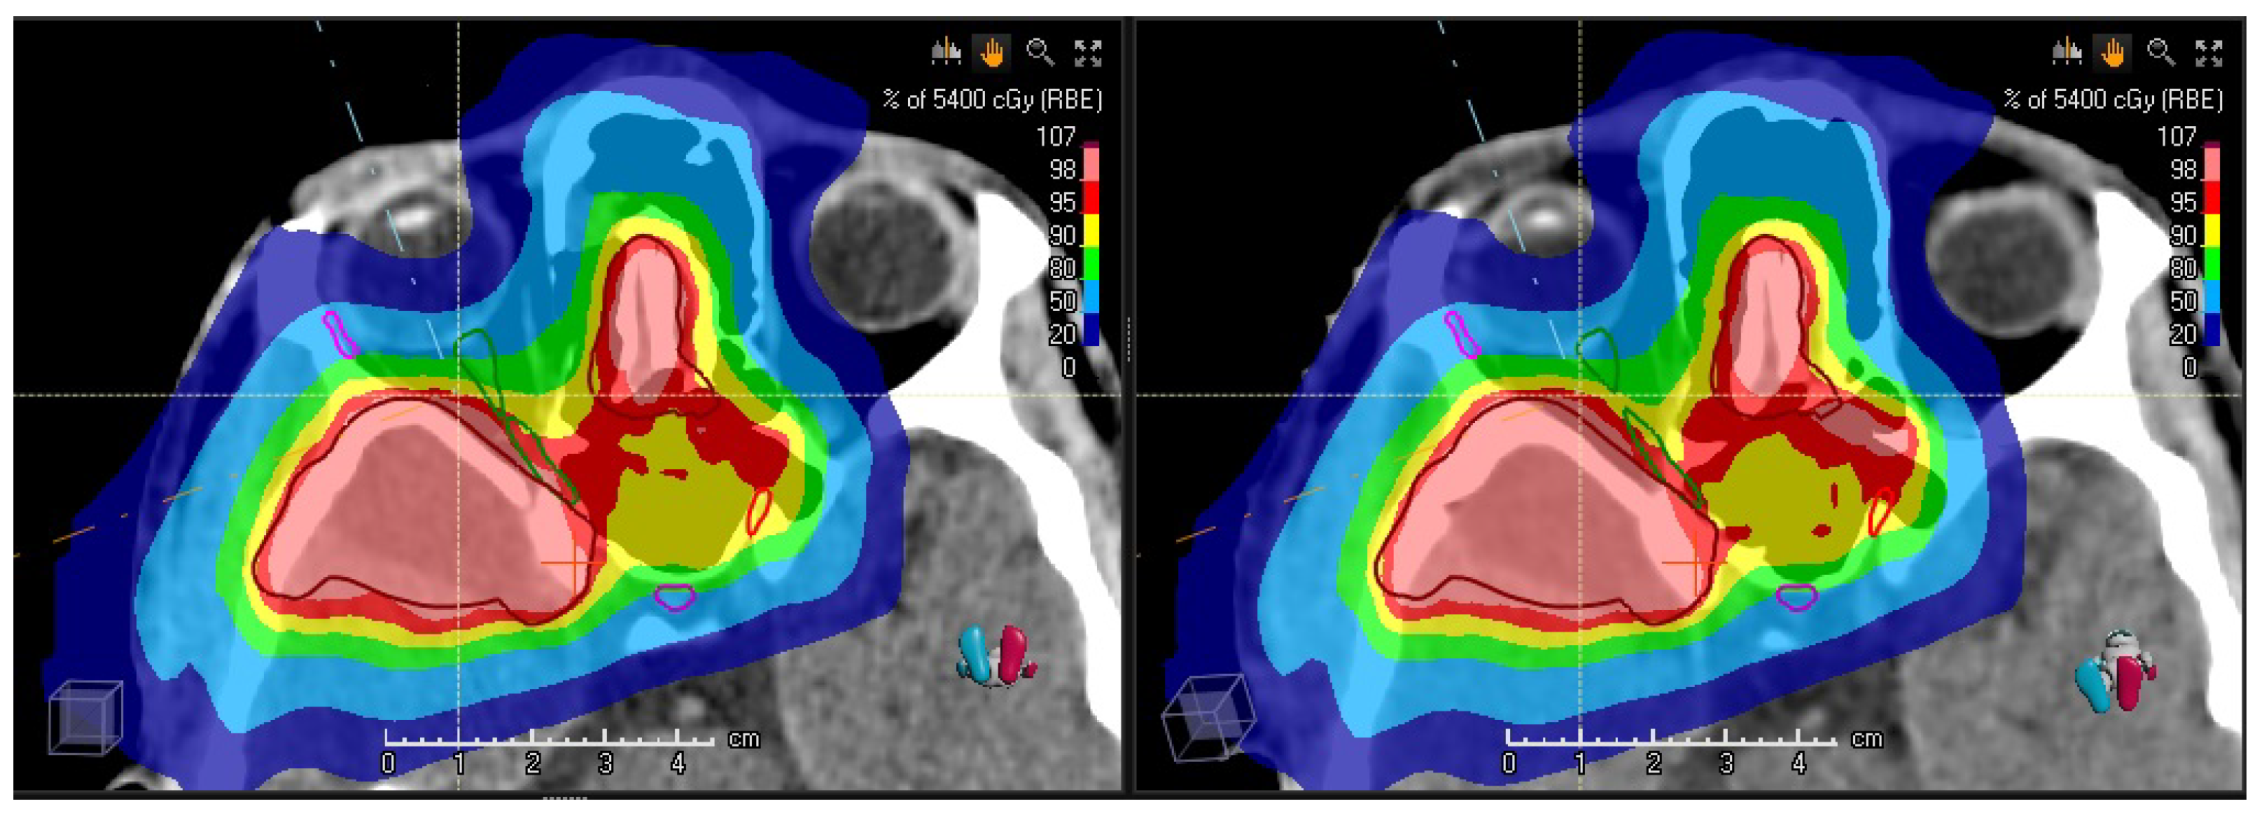

3.1. Validation of the Synthetic CTs—Results

3.2. Preliminary Results of the Clinical Study

| Quantity | ROI | Unit | rCT | vCT | sCT | Clinical Goal |

|---|---|---|---|---|---|---|

| PTV | % | 98.3 | 96.7 | 96.8 | 95.0 | |

| PTV | GyRBE | 55.7 | 55.7 | 55.8 | 57.8 | |

| PTV | GyRBE | 54.0 | 53.9 | 53.9 | ≈54 | |

| right optical nerve | GyRBE | 52.5 | 53.3 | 52.5 | 56.0 | |

| left optical nerve | GyRBE | 52.5 | 52.1 | 52.1 | 56.0 | |

| chiasm | GyRBE | 52.3 | 51.8 | 51.7 | 56.0 | |

| pituitary | GyRBE | 38.5 | 38.6 | 37.6 | 40 |